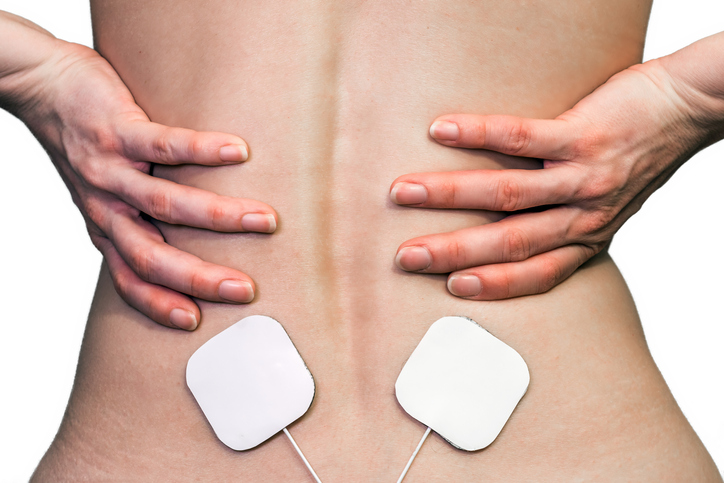

Sciatica and lower back pain

Sciatica and lower back pain